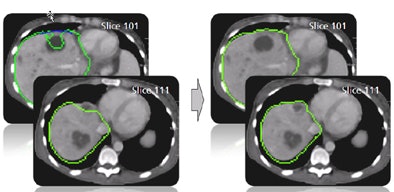

| Step one (above) requires the user to simply draw the actual border of the liver in one slice. The extrapolation of this user contour extracts equidistant seed points, connects seed points using a live-wire segmentation algorithm, and replaces part of the initial contour. Below, the user contour is extrapolated to neighboring slices for 3D correction. A search for seed points is performed in a given search area using a block matching algorithm. The seed points are connected using the live-wire algorithm, and this process continues until termination criteria are met. |

![]() |